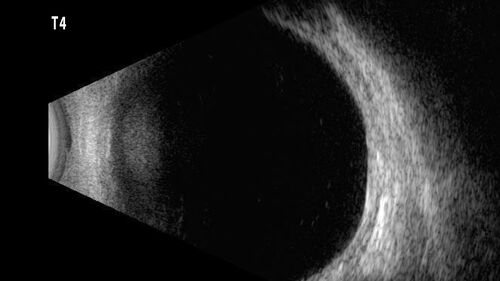

32 year old with peripheral CHRPE